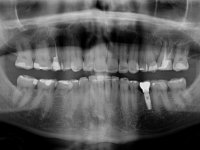

Paciente do sexo masculino, com 36 anos, não fumador. Fez tratamento ortodôntico e reabilitou esteticamente o sector anterior com restaurações em resina composta. As restaurações apresentavam um aumento vertical médio de 2 mm em relação o bordo incisal. Apresentavam-se esteticamente satisfatórias, mas com algumas fraturas incisais. O dente 1.5 apresentava um processo apical e o dente 2.6 apresentava tratamento endodôntico e uma lesão endo-periodontal. No maxilar inferior no local do dente 3.5 apresentava um implante com uma coroa aparafusada e o dente 8.5 ainda estava presente em boca com agenesia do dente 4.5. O paciente apresentava uma ligeira perda da dimensão vertical da oclusão provavelmente associada a um visível desgaste das superfícies oclusais. O periodonto era espesso e apresentava uma excelente higiene oral.

Após análise clínica e imagiológica foi proposto ao paciente recuperar a dimensão vertical da oclusão essencialmente à custa de incrementos oclusais inferiores utilizando “overlays” no sector posterior e facetas no sector anterior. A coroa aparafusada sobre o implante 3.5 seria substituída, no sentido de acompanhar este incremento. Na maxila o dente 2.6 teria extração indicada e posteriormente seria reabilitado com um implante e respetiva coroa. No sentido de reabilitar esteticamente o paciente duma forma minimamente invasiva, foi proposta a colocação de facetas feldespáticas no sector antero-superior. O objetivo de aumentar ligeiramente a D.V.O., teria como função “proteger” eficazmente o sector antero-superior.

Realizado o diagnóstico e tomada a decisão quanto ao tratamento a executar, tornou-se importante definir qual a sequência de trabalho a adotar no sentido de conseguir a reabilitação da D.V.O. (V.D.O), de forma progressiva e equilibrada. Na primeira fase fez-se uma pré-impressão da arcada inferior com silicone tipo “putty” e em seguida realizou-se o preparo dentário de todo o sector posterior. O preparo para os overlays foi feito coronalmente à linha amelo cementaria no sentido de ser o mais conservador possível. A impressão foi feita com técnica de dupla mistura após afastamento gengival realizado com pasta de caulino. A provisória foi realizada com resina composta de polimerização dual. Em laboratório foram realizados os overlays após se ter aberto ligeiramente (1,5mm) a D.V.O. nos modelos montados em articulador semi-ajustável. Simultaneamente o sector antero-inferior foi encerado no sentido de acompanhar este aumento da D.V.O. Também foi confecionada uma chave de silicone translucido para posterior confeção dos provisórios antero-inferiores. Em boca foi primeiro realizada a provisionalização dos dentes anteriores utilizando resina composta previamente aquecida após preparação das superfícies dentárias para a adesão. Foi colocado o dique de borracha para promover o isolamento absoluto e posteriormente foram colados os overlays. Em laboratório foi realizada nova chave de silicone para confecionar os provisórios antero-superiores. Seguidamente em boca foram preparados os seis dentes antero-superiores após colocação do fio de afastamento gengival. Feita a preparação adequada das superfícies dentárias foi realizada a impressão com técnica de dupla mistura e a respetiva provisória. Em laboratório foram confecionadas 6 facetas feldespáticas num modelo de trabalho tipo “Geller”. A provisória foi removida e as facetas foram coladas em boca utilizando um isolamento relativo competente. Esta opção foi tomada em virtude de uma prévia experiencia negativa com a colocação do dique de borracha na mandibula. Após a colagem dos laminados antero-superiores foram dadas 12 semanas para avaliar a adaptação do paciente à nova situação e então iniciar a confeção das facetas antero-inferiores. Após colocação do fio de afastamento gengival. foram feitos os preparos dentários adequados e em seguida foi feita a impressão. Também foi feita a preparação do dente 3.4 que, entretanto, tinha sofrido uma fratura do overlay. As facetas e a restauração do 3.4 foram realizadas num modelo de trabalho tipo “Geller”. Após remoção da provisória, as facetas foram coladas em boca, utilizando um isolamento relativo pelas razões apontadas anteriormente. Após colocação do trabalho o paciente foi reabilitado por outros colegas com um implante na zona do 2.6 e substituição da coroa aparafusada sobre o implante colocado no local do 3.5. Posteriormente surgiram fraturas nos overlays dos dentes 4.7 e 3.7 que foram reabilitados com overlays em Zr.